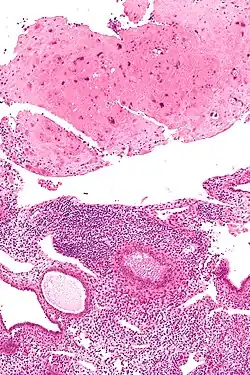

Micrograph of a placental site nodule (top of image). H&E stain.

Typically, they consist of pink (hyaline) material using the standard stain and contain few cells. Bizarre multinucleated cells may be present; however, there is no mitotic activity. The differential diagnosis includes (cervical) squamous cell carcinoma, gestational trophoblastic disease, and exaggerated placental site.